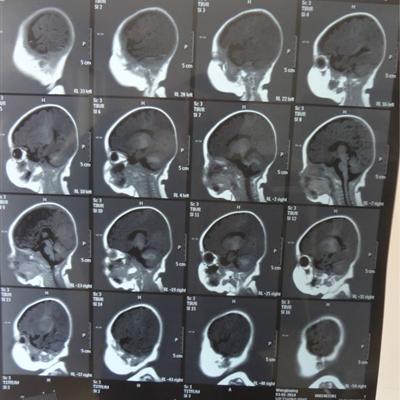

How long can benign brain tumor live?

First: the first one is the survival period of patients, which is often related to the method of treatment and the patient's own physical state. Whether the treatment method is appropriate is a very important factor, for patients with advanced brain cancer, there will be a lot of treatment methods.

Second, for some patients, it may not be recommended to remove the tumor for surgery, but the patient's physical condition should be taken into consideration, so radiotherapy or chemotherapy is generally adopted, and sometimes radiotherapy is the main treatment, and the corresponding chemotherapy is the auxiliary treatment, and the joint treatment of traditional Chinese medicine is also added.